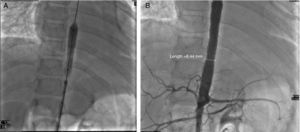

Glucocorticoids and methotrexate were initiated. Cardiac catheterization was performed due to the presence of more than 3 sites of stenosis. We documented diastolic dysfunction, mild mitral regurgitation; severe stenosis of the thoracoabdominal aorta with a gradient of 50mmHg and nonsevere renal artery stenosis (10mmHg gradient) (Fig. 2A and B). Angioplasty was performed in which two stents were placed in the stenotic area, with a postsurgical gradient of 0 (Fig. 3A and B). She is currently asymptomatic with no residual gradient. She no longer receives glucocorticoids but is receiving methotrexate, folic acid, vitamins A, C and D, aspirin, furosemide, spironolactone, and captopril.